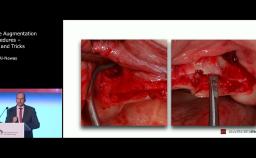

Peer Kämmerer introduces a case in which a patient did only come back 1.5 years instead of 4 months after extensive bone grafting, resulting in severe resorption of the iliac graft. In combination with a highly atrophic maxilla, financial constraints and poor compliance due to cognitive disorders this case presented many challenges that were tackled using zygomatic implants.